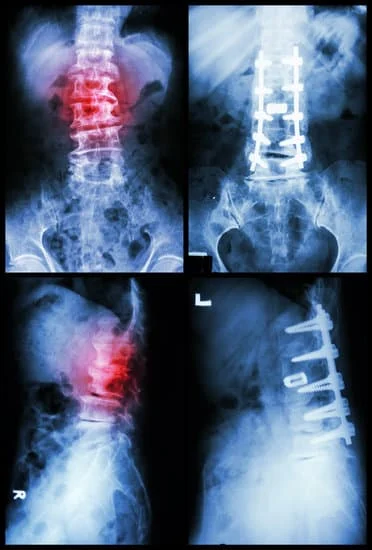

• Spinal Surgery, Spondylosis, Arthritis & Osteoporosis Treatment